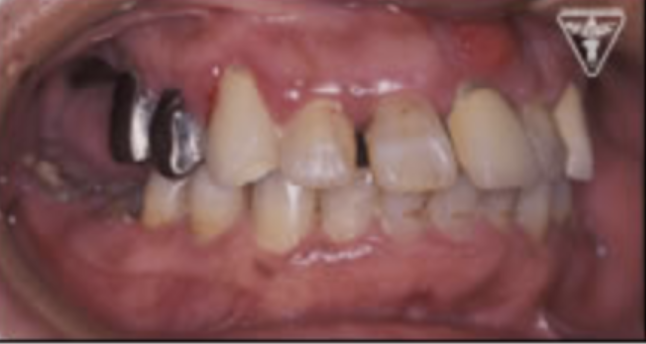

人工歯根と接合するアバットメントを示します。

治療過程

抜歯後、歯周病処置、歯内療法処置、咬合高径改善、プロビジュナルレストレーションを経て最終補綴をおこないました。